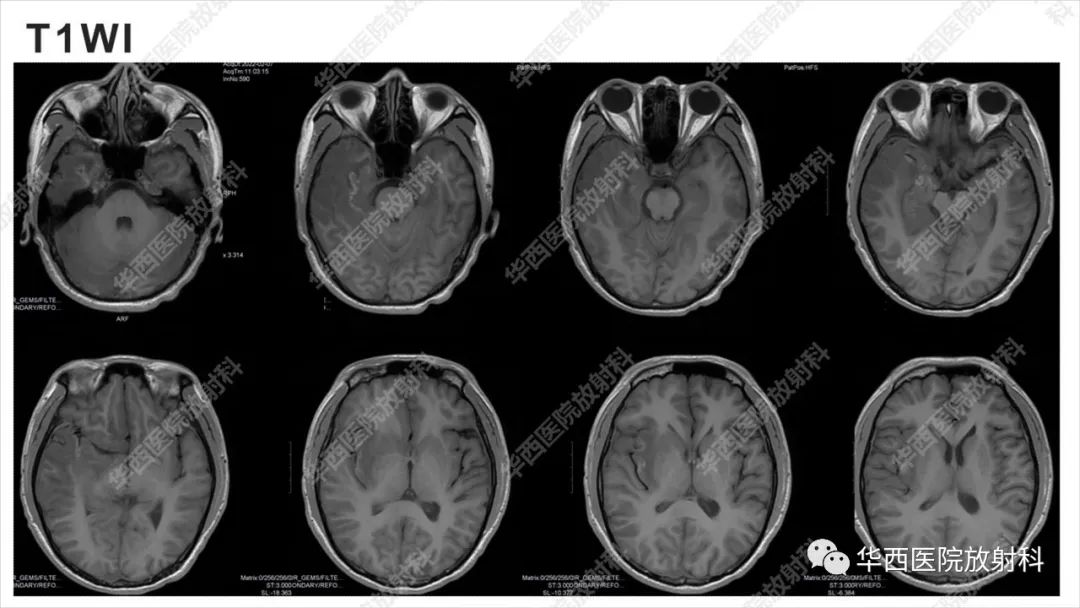

【病例】出血坏死性病毒脑膜脑炎1例CT及MR影像学表现和鉴别诊断-1